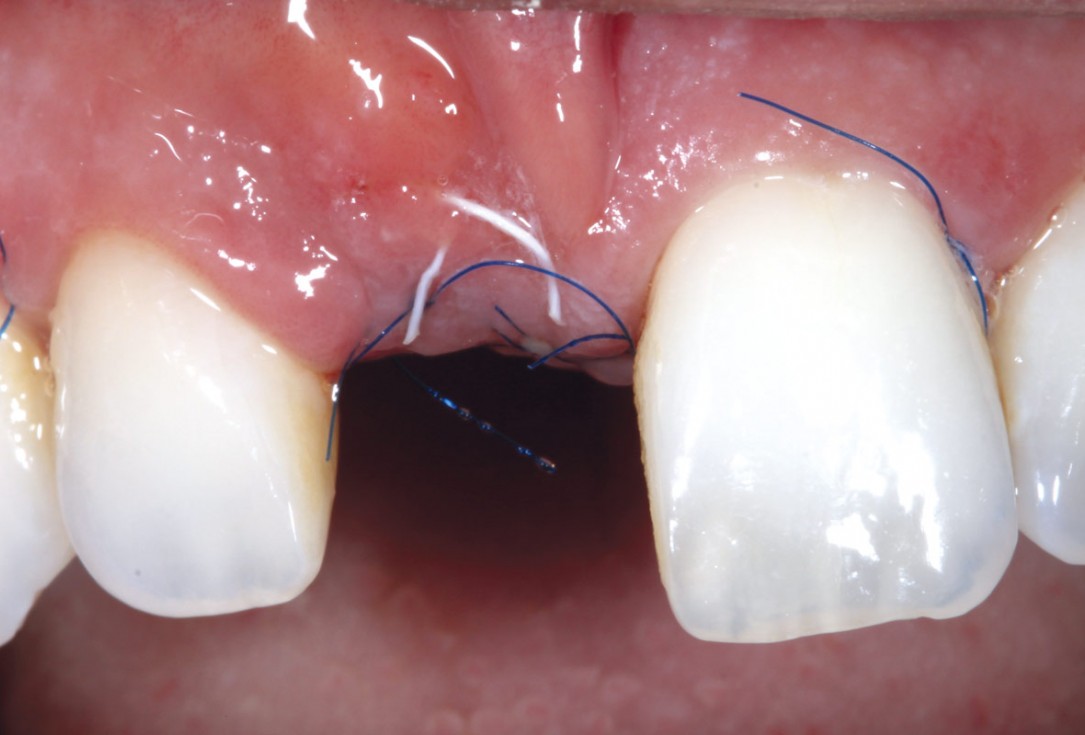

Initial clinical situation with single tooth gap in regio 21